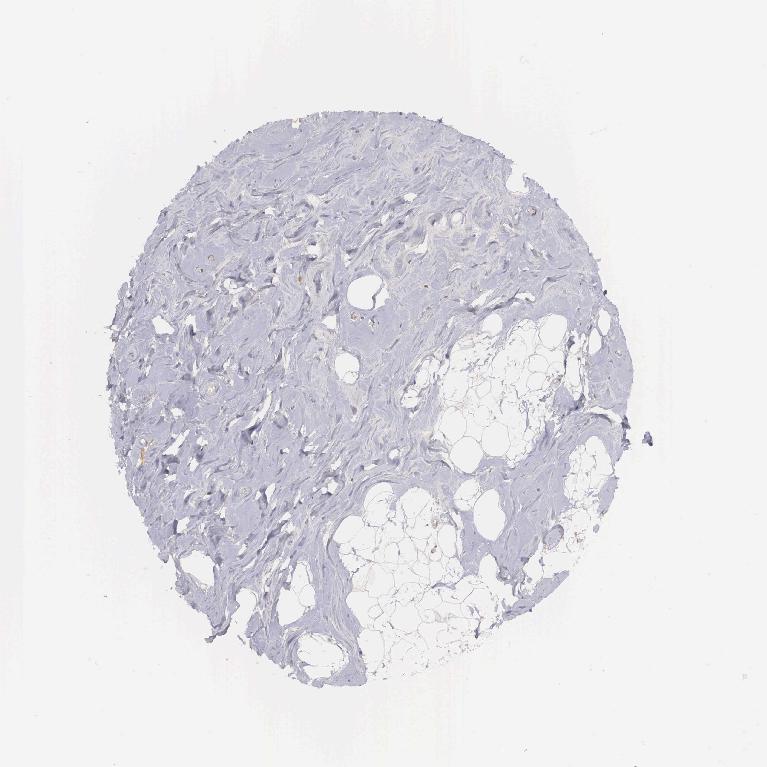

ADIPOSE TISSUE - Antibody stainingi

Antibody staining in the annotated cell types in the current human tissue is reported as not detected, low, medium, or high, based on conventional immunohistochemistry profiling in selected tissues. This score is based on the combination of the staining intensity and fraction of stained cells.

Each image is clickable and will lead to virtual microscopy that enables deeper exploration of all samples and also displays staining intensity scores, fraction scores and subcellular localization as well as patient and tissue information for each sample.

Antibody HPA000545

Adipocytes Not detected